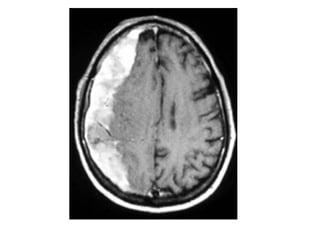

CT+C , infarction in the territory of the MCA , there is extensive gyral

enhancement (luxury perfusion) , sometimes this luxury perfusion

may lead to confusion with tumoral enhancement

-Enhanced CT images of a

patient with an infarction

in the territory of the MCA

-There is extensive gyral

enhancement (luxury

perfusion)

-Sometimes this luxury

perfusion may lead to

confusion with tumoral

enhancement

-Luxury perfusion used to

describe the dilation of

numerous vascular

channels observed within

the relatively avascular

infarcted area of the brain

24-48 h after an ischemic

stroke , these are

predominantly venous

channels but arterial

channels open up as well

5-Arterial Occlusion :